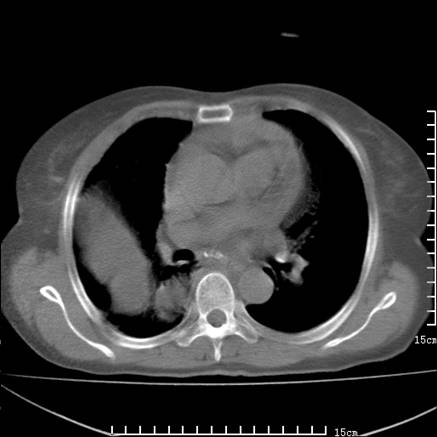

女,王某,58岁,咳嗽三个月余,基层医院二个月前诊为肺结核,用抗结核药二个月无明显疗效。

心包积液致肺瘀血.右侧周围型肺癌伴肺内转移,中间裂积液,叶间胸膜肥厚.右上肺大泡,右侧胸膜肥厚.

双肺继发型tb,心功能不全并肺淤血、心包、双侧叶间裂积液,肺大泡,右下胸膜肥厚钙化。